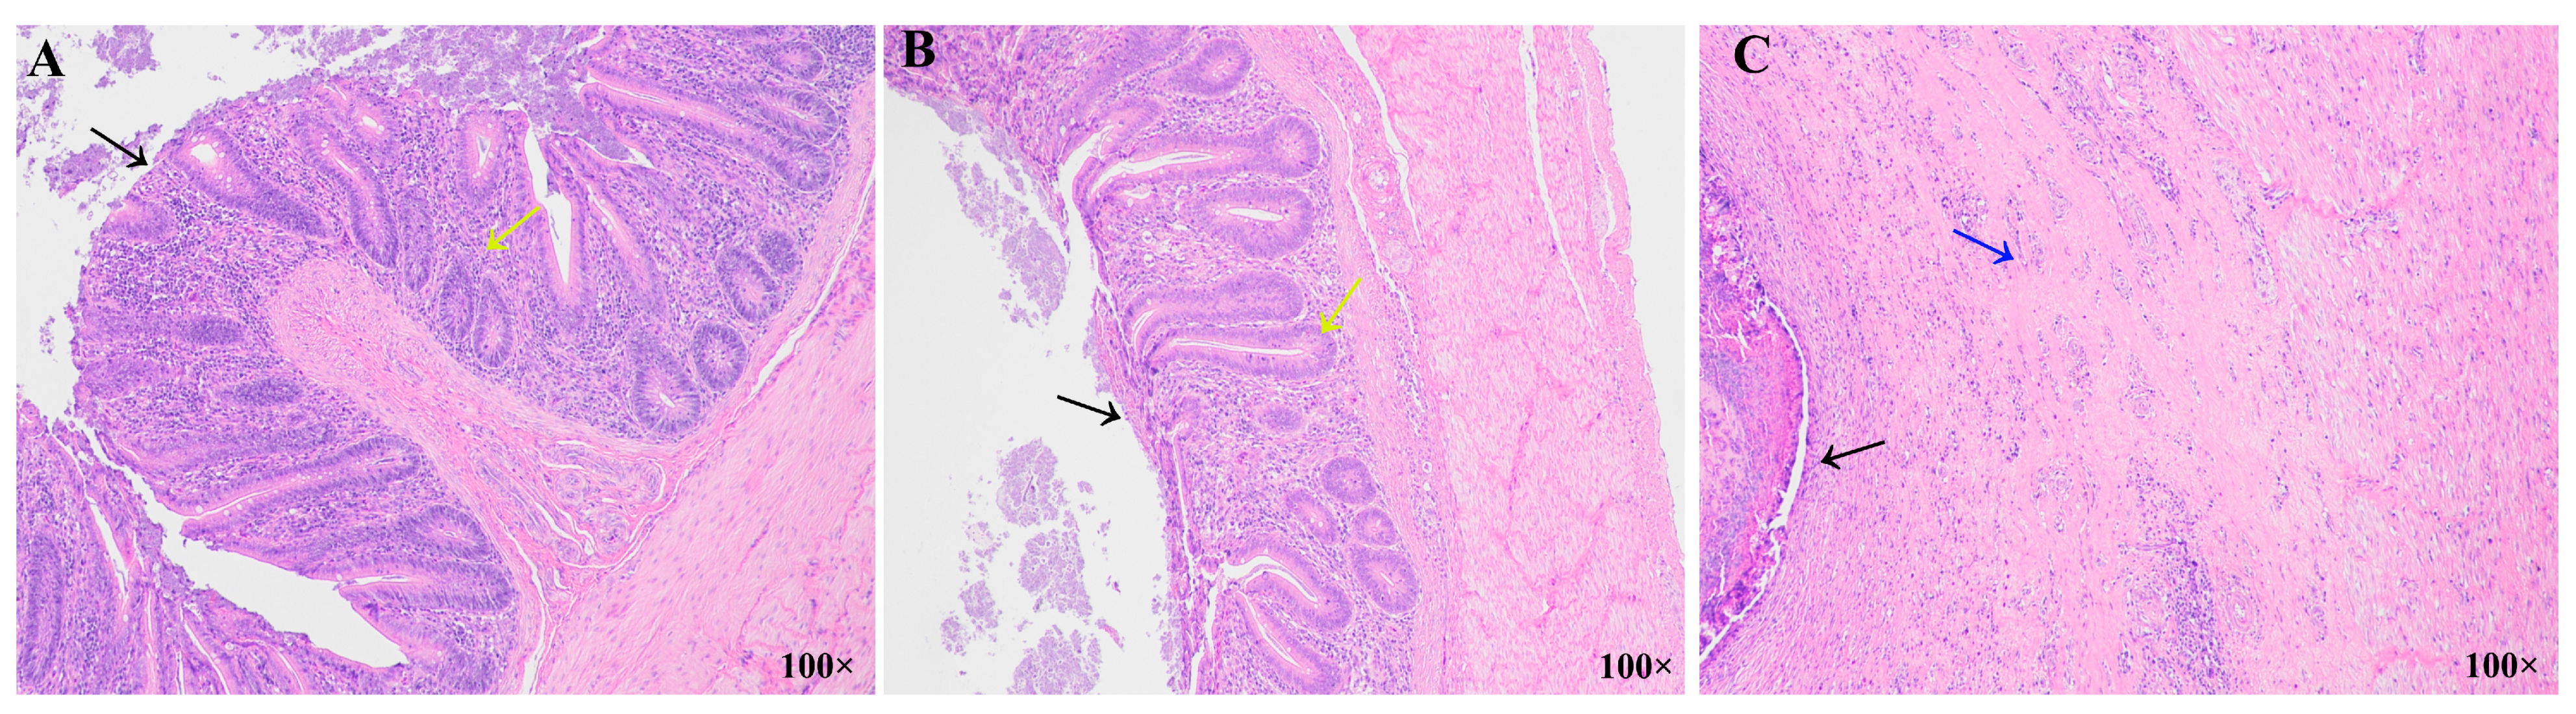

3.3. Histopathological Analysis of the Ceca in Different Resistance Groups During Recovery